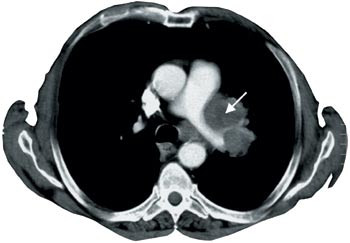

40 undersøkelser (95 %) var utført med intravenøs kontrastinfusjon, mens to var utført uten. Alvorlig kontrastmiddelallergi ca. 20 år tidligere, var oppgitt som årsak hos en av disse. Tre undersøkelser var utført med serier både før og etter kontrastinfusjon. Kontrastfylling i mediastinale kar ble vurdert å være suboptimal hos sju (18 %), men tilfredsstillende hos de resterende 33 (82 %) (fig 1).

Kun 27 (63 %) av undersøkelsene hadde godkjent kvalitet. Dårlig kontrastfylling i karene i mediastinum eller mye bevegelsesartefakter på grunn av langsomt opptak var vanlige årsaker til ikke-godkjent kvalitet (fig 2). Verken de fire undersøkelsene der bare tumor var dekket av serien, eller de to utført helt uten intravenøst kontrastmiddel, ble godkjent. Kvaliteten på undersøkelsen ble likevel vurdert tilstrekkelig god for den aktuelle problemstillingen i tre av sju tilfeller der det på tross av infusjon ikke var optimal fylling av kontrast i mediastinale kar. Andel godkjente undersøkelser var større der spiral-CT var benyttet (22 av 25 undersøkelser, 88 %), sammenliknet med konvensjonell, aksial skanning (fem av 17 undersøkelser, 29 %). Av godkjente undersøkelser var en fra privat røntgeninstitutt, 11 fra lokal- og 15 fra sentral- eller regionsykehus. Av ikke-godkjente undersøkelser (n = 15) var to fra private røntgeninstitutt, 10 fra lokal- og tre fra sentral- eller regionsykehus.